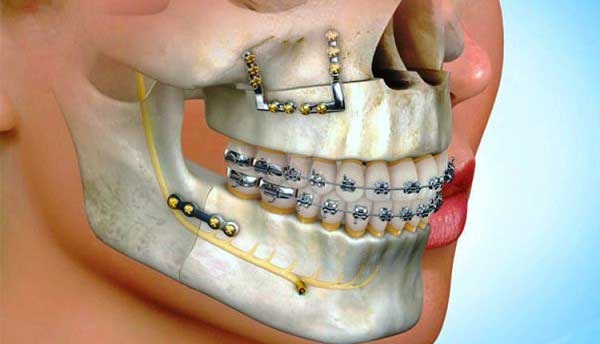

Some orthodontic issues require additional care, such as removing one or more teeth or having jaw surgery (orthognathic surgery). In these cases, your orthodontist will work with an oral and maxillofacial surgeon to ensure the best results. Often, early orthodontic consultations can help reduce the need for these more serious procedures, and may even make them unnecessary. Your orthodontist will discuss the options available to you during your initial consultation. They will take X-rays, photographs and digital scans of your teeth to diagnose the condition and prepare a treatment plan.

Surgically correcting misaligned jaws can alleviate pain, improve chewing and speaking abilities and enhance facial appearance. Corrective jaw surgery is performed while you are under general anesthesia in a hospital, ambulatory surgery center or oral and maxillofacial surgeon’s office. The procedure generally takes one to several hours.

During the operation, your orthodontist tallahassee fl separates and repositions the jaw to align it properly. Depending on your specific needs, bone may be added, reshaped or removed. Tiny screws and metal plates are often used to hold the jaw in place during healing.